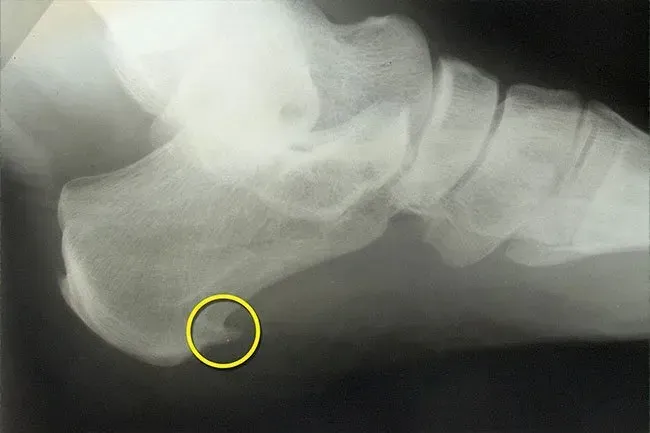

Éperons osseux

Vous pourriez confondre ces croissances osseuses lisses pour les oignons. Avec les oignons, les os sont déplacés. Les éperons osseux, d'autre part, sont des croissances au bord des os de votre pied souvent à mi-pied ou à un gros orteil. S'ils deviennent assez grands, ils pousseront les nerfs et les tissus à proximité et feront mal. L'arthrose ou un tendon ou un ligament tendu peut provoquer ces croissances qui sont plus courantes à mesure que vous vieillissez, surtout après 60 ans.